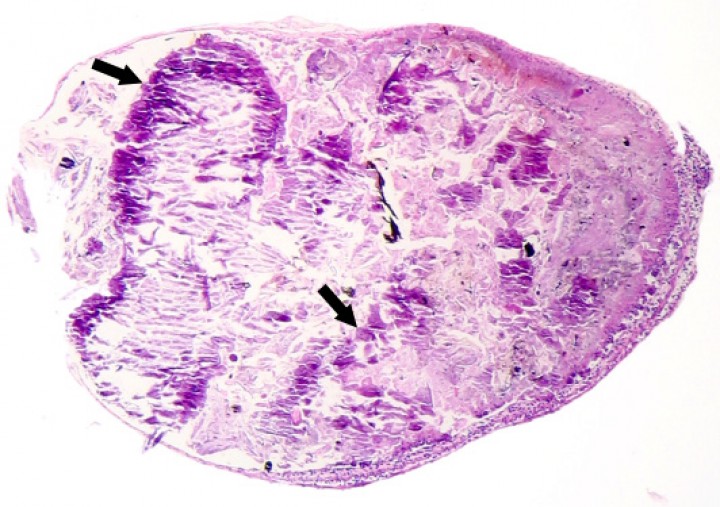

Se observaron 8 neoplasias, diagnosticadas en 6 de los 131 (4,6%) anfibios. Dos correspondían a adenocarcinomas sin evidencias de metástasis: uno intestinal en una rana dardo verdinegra (Dendrobates auratus) (Fig. 8), y otro en un tejido no identificable en un sapo buey (Rhinella schneideri); este último mostraba, además, hemangiomas en el pulmón (Fig. 9). El adenocarcinoma intestinal de la rana dardo verdinegra (Dendrobates auratus) consistía en una proliferación mal delimitada y no encapsulada de enterocitos que formaban criptas y glándulas variablemente dilatadas o, raramente, nidos diminutos compactos que invadían de forma amplia todas las capas del segmento intestinal afectado (Fig. 8) y mostraban anisocitosis, anisocariosis, pleomorfismo y anaplasia bajos a moderados, sin actividad mitótica aparente. Otros 3 anfibios padecieron neoplasias hematopoyéticas: un linfoma multicéntrico con componente epiteliotrópico en una rana tomate (Fig. 10) y dos neoplasias de células redondas no identificables de forma clara mediante la tinción rutinaria en un sapillo balear (Alytes muletensis) y un axolote (Ambystoma mexicanum). Otro sapillo balear (Alytes muletensis) mostraba una proliferación multicéntrica benigna de epitelio renal tubular (Fig. 11) organizado en estructuras tubulares, papilares y quísticas (Fig. 12), compatible con adenomatosis renal (adenomas múltiples); se observó atipia celular en escasas células neoplásicas y en células epiteliales de túbulos no neoplásicos. Adicionalmente, en este sapillo balear (Alytes muletensis) se apreció un foco hepático bien delimitado y no encapsulado de proliferación de hepatocitos compatible con hiperplasia nodular o un hepatoma; la ausencia de tríadas portales dentro de esta neoplasia es compatible con un hepatoma (Fig. 13).

<p>Riñón; sapillo balear (<em>Alytes muletensis</em>). La sección de riñón del sapillo en la Figura 11 está casi completamente reemplazada por un adenoma con zonas papilares densas (P) y zonas quísticas (Q), que comprime el tejido renal no neoplásico restante (cabezas de flecha). Hematoxilina-eosina, x48.</p>

Riñón; sapillo balear (Alytes muletensis). La sección de riñón del sapillo en la Figura 11 está casi completamente reemplazada por un adenoma con zonas papilares densas (P) y zonas quísticas (Q), que comprime el tejido renal no neoplásico restante (cabezas de flecha). Hematoxilina-eosina, x48.